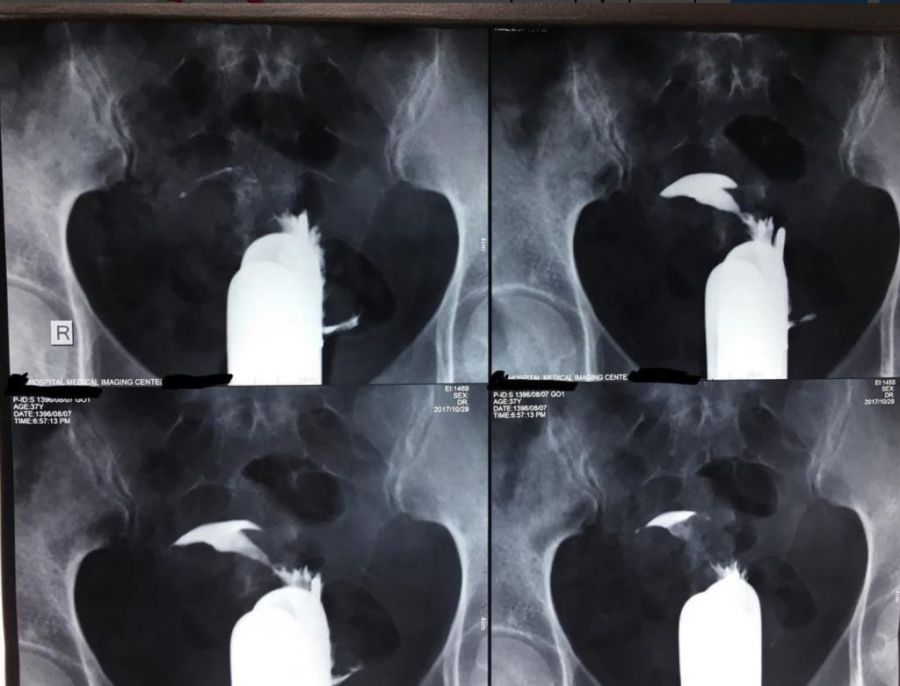

آمادگی سونو گرافی هیسترو سالپنکوگرافی ؛ هیستروسالپنگوگرام یا سونو گرافی هیسترو سالپنکوگرافی به پزشک اجازه می دهد تا دیواره های داخلی رحم و لوله های فالوپ را بررسی کند. این روش جزئی برای ارائه اطلاعاتی در مورد شکل و کانتور حفره آندومتر (رحم) یا مستند سازی وجود پولیپ آندومتر، لیومیومات (فیبروم) یا اسکار طراحی شده است. علاوه بر این، این روش تعیین می کند که آیا لوله های فالوپ ثبت شده (باز) هستند یا خیر.

مسدود شدن لوله فالوپ یا رشد در رحم می تواند شانس بارداری شما را کاهش دهد. اگر لوله های فالوپ شما مسدود شده باشد، اسپرم نمی تواند به تخمک برسد. در سونو گرافی هیسترو سالپنکوگرافی از اشعه ایکس و یک رنگ مخصوص برای تشخیص بافت اسکار، پولیپ، فیبروم و سایر تودههایی که ممکن است لولههای شما را مسدود کرده یا مانع از کاشت صحیح تخمک بارور شده در رحم شما شوند، استفاده میکند.

روی یک میز دراز خواهید کشید. پاهای شما در رکاب قرار می گیرد. ارائه دهنده مراقبت های بهداشتی شما یک دستکش برای بررسی واژن و دهانه رحم شما وارد می کند. یک اسپکولوم گرم شده به آرامی وارد می شود تا واژن شما باز شود . یک کاتتر به دهانه رحم شما وارد می شود. سپس پزشک مایع حاجب را از طریق کاتتر تزریق می کند و چندین عکس اشعه ایکس گرفته می شود. بعد از عکس برداری با اشعه ایکس، کاتتر از بدن شما خارج می شود. برای جذب خون یا مایع حاجب که پس از عمل تخلیه می شود، باید از نوار بهداشتی استفاده کنید.